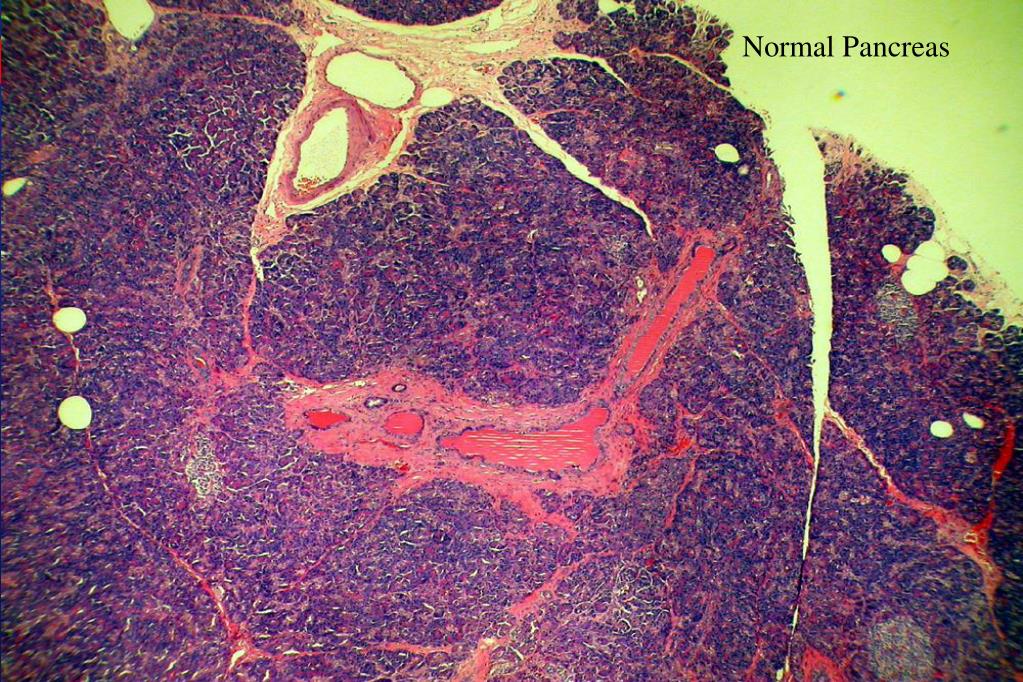

4. Normal Pancreas